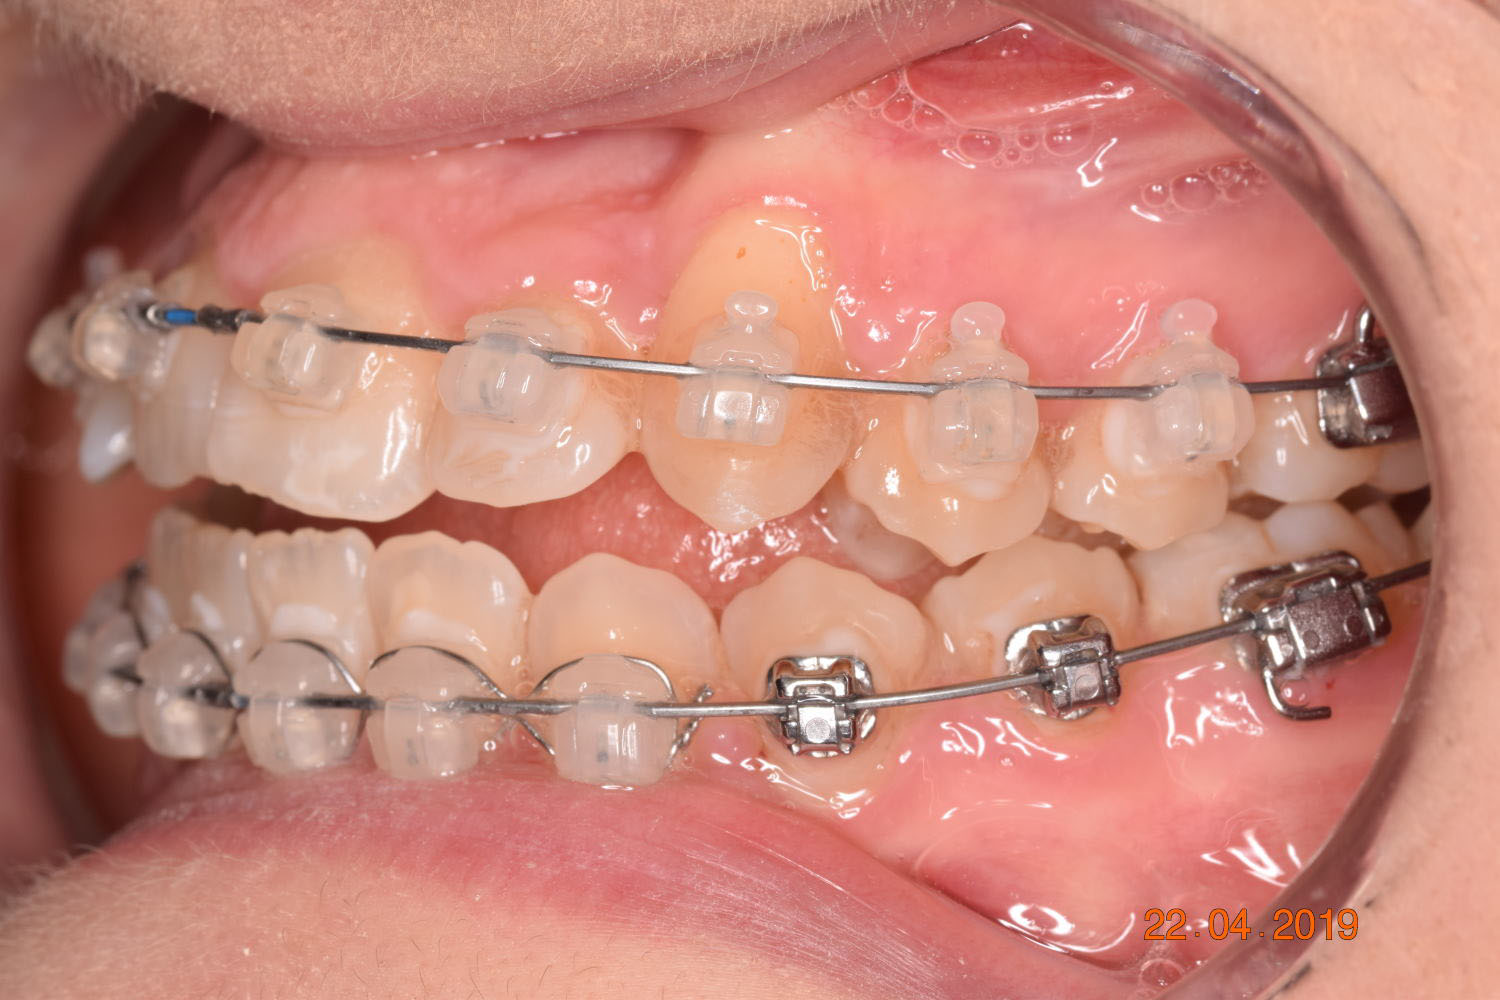

The treatment began in 2017. Given the patient’s preference for less visible brackets, Damon Clear brackets were selected. High torque upper cuspids and low torque upper incisors were chosen to offer the best torque control for upper arch development. For the lower arch, there were no alternative bracket configurations available. Bite turbos were applied to the upper second molars.

The results were unsatisfactory and the patient began losing interest in the treatment. Dr. Coca and the patient agreed to extend the treatment for six more months and then stop, regardless of the outcome.

Adhering to the principles of Face First Orthodontics, the primary objective was to increase midface support by expanding the upper maxilla, fixing the cross bite, and aligning the teeth. Closing the open bite was a secondary objective.